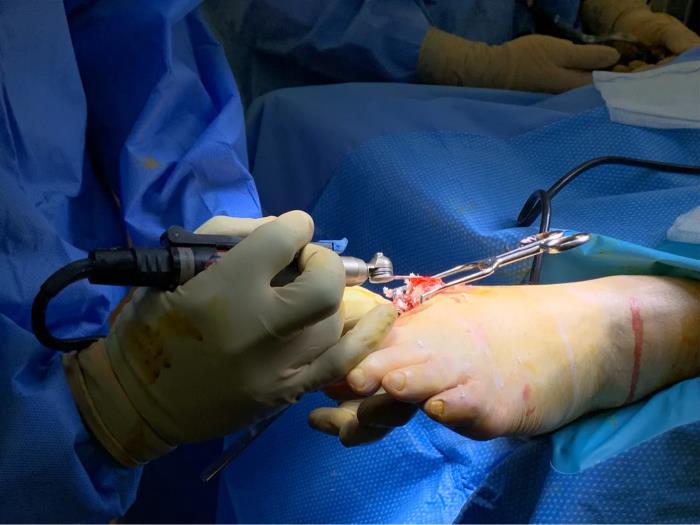

4 ,对于经过严格的保守治疗,都不能缓解患者的症状,而且疼痛严重的影响患者的正常生活的时候,我们选择进行手术治疗。

拇外翻手术的目的是为了恢复足部的外形,以及行走时的正常的足底应力分布,消除疼痛,改善行走功能。由于足部解剖比较复杂,而且每一位病人又具有各自的特殊性,手术难度相对于其它大关节来说,具有一定的挑战性,如同钟表师傅修理手表和修理座钟的区别,对于足踝专业的骨科大夫来说,就需要全面地掌握足踝疾病的理论知识和手术技术才能够做到得心应手,对付各种情况。

拇外翻手术包括足部的软组织平衡与骨性结构力线的重排,前者是对大脚趾周围韧带肌腱关节囊调整,后者只是对大脚趾的骨骼进行重新排列,再固定于正常的解剖位置,恢复正常的力线排列。单纯的切除内侧的突起是解决不了问题的,有时候还需要对其他脚趾进行处理。